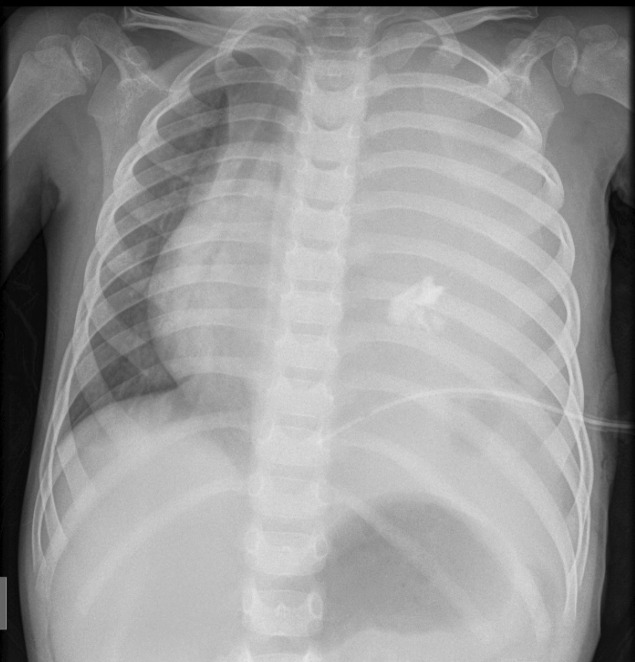

Teaching point: This is a review of the typical radiological features of a mature mediastinal teratoma with a rare presentation of spontaneous pleural rupture.

Abstract Image